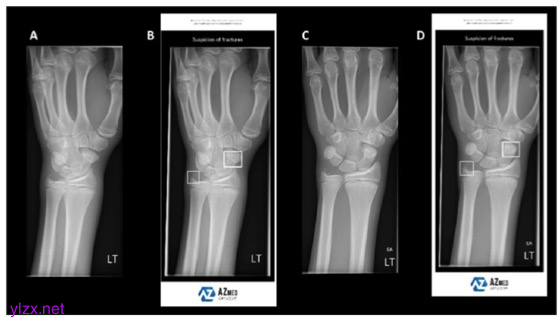

图 在这个例子中,左手腕视图(A)和(C)已经提交给AI解释。人工智能通过在各自的放射图像上显示边界框作为“覆盖”来标记儿童舟状骨和尺骨茎突骨折(B, D)。这些数据也被发送到PACS供放射学记者和临床医生审查